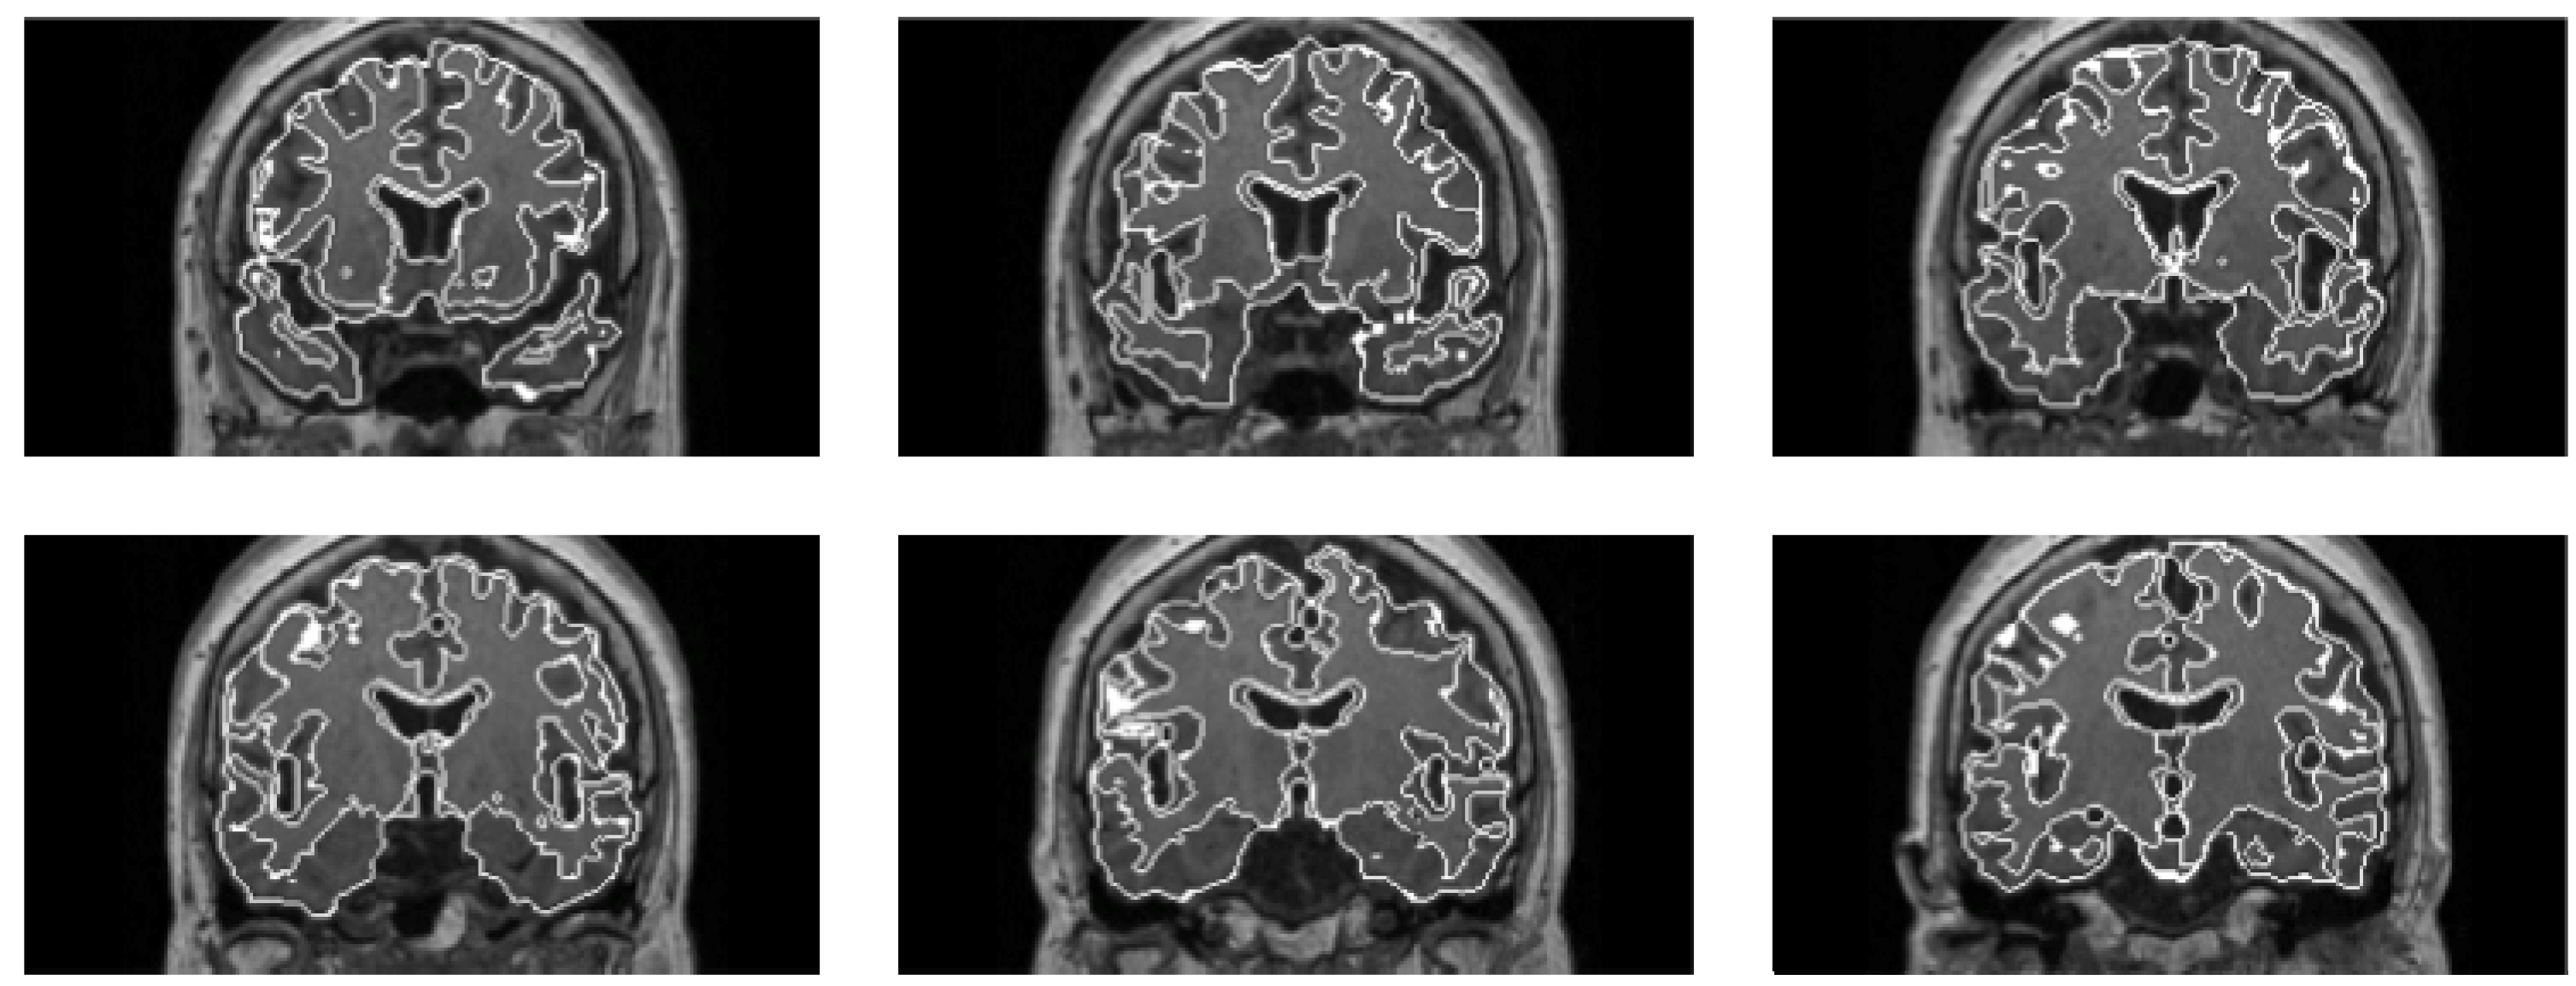

Figure 13 shows the segmentations of brain regions (outer white line) and white matter regions (inner white line) obtained by the proposed method from a non-AD patient in multiple coronal planes. As a result, the area under a ROC curve (Az value) obtained by the CAD system was 0.909 based on a leave-one-out test in identification of AD patients among 54 cases. The preliminary results showed that the proposed method may be promising for identification of AD patients.

Figure 13.

Segmentations of brain regions (outer white line) and white matter regions (inner white line) obtained by the proposed method from a non-AD patient in multiple coronal planes [27].

We attempt to develop a CAD system for identification of patients with cerebral atrophy due to Alzheimer’s disease based on a pattern recognition technique using 3-D MR images. Our CAD system consists of determination of atrophic image features and identification of AD patients. First, brain, white matter and gray matter regions were determined based on a level set method. Second, CSF regions in cerebral sulci and LVs were extracted by wrapping the brain with a level set function. Third, the cerebral cortical thickness was measured based on normal vectors as a distance from the white matter surface to the brain surface. To select mean cortical thicknesses in the most effective subregions for distinguishing AD patients from non-AD patients, we employed a Golub statistic [85,86], which can be interpreted as the degree of separation between the two classes. Finally, AD cases were classified from non-AD cases based on a support vector machine (SVM) classifier, which learned atrophic image features, i.e., white matter and gray matter volumes, CSF volume, and cerebral cortical thickness. The SVM classifier was constructed with a Gaussian kernel exp (−γ||x−y||2) by using an open source software SVM light [87].